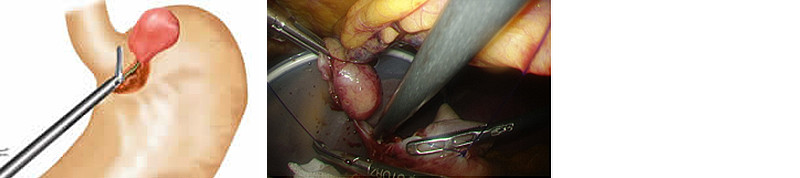

当科では、腫瘍の大きさが5cm以下の場合には、従来より腹腔鏡を用いた外科手術を行っております。腹腔鏡手術は開腹手術と比べておなかの傷を小さくでき、術後の痛みが少なく回復が早いという利点があります(図1)。さらに最近ではGISTに対し、胃内視鏡と腹腔鏡を組み合わせたLECS(Laparoscopy Endoscopy Cooperative Surgery:腹腔鏡・内視鏡合同手術)を導入し、良好な結果を得ています(図2)。特に胃内発育型のGISTに対する従来の腹腔鏡のみを用いた手術では、正常な胃壁の余分な切除範囲が大きくなり、術後に胃の変形を来すことがありました。LECSでは、消化器内科医が胃内視鏡を用いてGIST周囲の胃壁を切ることにより、正常胃壁の切除を最小限にとどめることができます。また、胃の入り口近くにGISTが存在する場合には、従来法では噴門側胃切除(胃の上部を1/2程度切除する方法)が必要でしたが、LECSを用いることにより部分切除が可能となりました。腫瘍を切除した後は、腹腔鏡手術にて胃壁を縫合閉鎖します。この方法により、最小限の胃部分切除が可能となり、また術後の胃の変形を来しにくくなりました(図3~4)。

図3 LECSの流れ

- 1.内視鏡操作(消化内科医により胃カメラで胃の粘膜側(内側)から腫瘍周囲を切開します)

- 2.腹腔鏡操作(消化器外科医により腹腔鏡下に胃の漿膜側(外側)から腫瘍周囲を切開します)

- 3.胃壁の閉鎖(消化器外科医により腹腔鏡下に胃の切除部分を縫合閉鎖します)

図4 摘出標本 約2cmの大きさの胃GIST